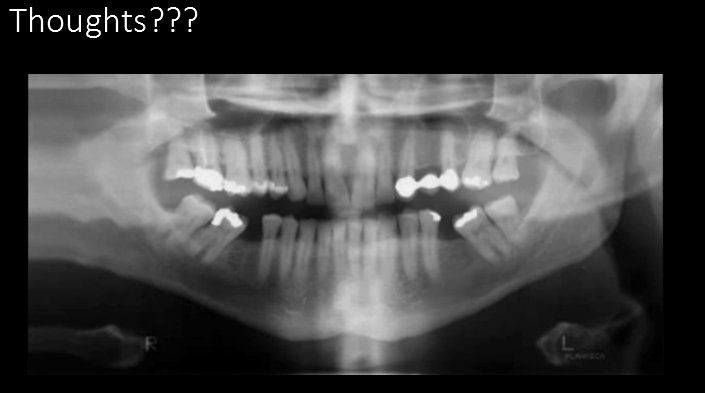

What error (s) do we see here?

A. Head rotated or twisted to right more

B. Head rotated or twisted to the left more

C. Chin too high

D. Chin too low